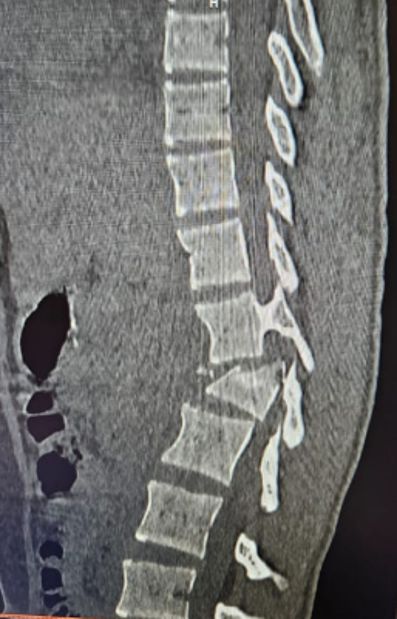

Emergency or planned surgery for injuries to the spine caused by accidents, falls, or sports trauma.

Broken bones are stabilized with screws, rods, or cages to protect the spinal cord and restore alignment.